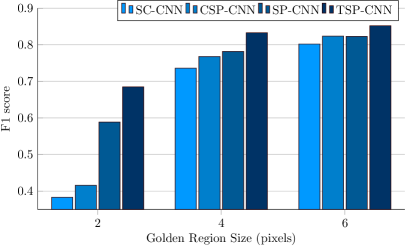

Note that the results reported in Table III and Fig. 11 use the same Golden Region specified in Section IV-B: pixels for the UW Dataset consistent with existing literature [5]. To investigate the effect of Golden Region selection, we report F1 scores generated by selecting different Golden Region sizes for the UW dataset in Fig. 13. We select the SC-, CSP-, SP- and TSP-CNN to conduct the experiments as they are the top-4 methods from Table III. From Fig. 13, as expected, F1 score increases with an increase in the golden region size. However, for a fixed Golden Region size, it is the relative performance of different methods that matters and as is evident from Fig. 13, this trend remains unchanged. In fact, with a smaller Golden Region such as , the SC-CNN and CSP-CNN performance degrades heavily even as the SP-CNN and TSP-CNN exhibit a much more graceful decay emphasizing higher spatial accuracy of (T)SP-CNN.